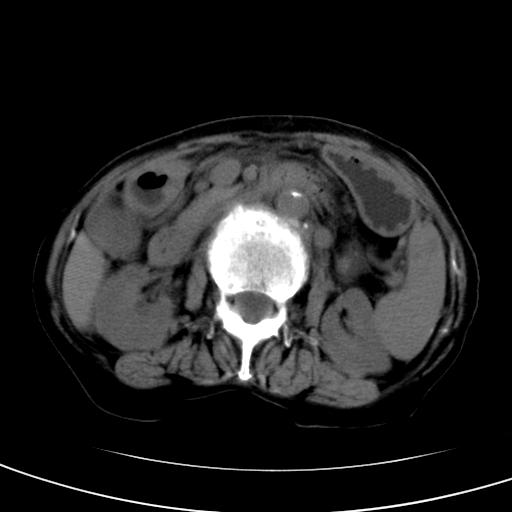

以下是引用wolft在2008-3-5 12:30:00的发言:[br]肝脏未见明显肿块影,但肝左叶增大,跨越腹中线到达脾胃前,且有一血管过去,考虑为先天变异:獭尾肝,胆囊为慢性胆囊炎急发,但胰腺头颈部有增大,密度不均匀,应该ct增强一下。

以下是引用zjzjr在2008-3-5 16:41:00的发言:[br]1.考虑慢性胰腺炎急性发作,建议增强除外占位性病变.[br]2.胆囊结石伴胆囊炎.[br]3.肝内胆管结石.